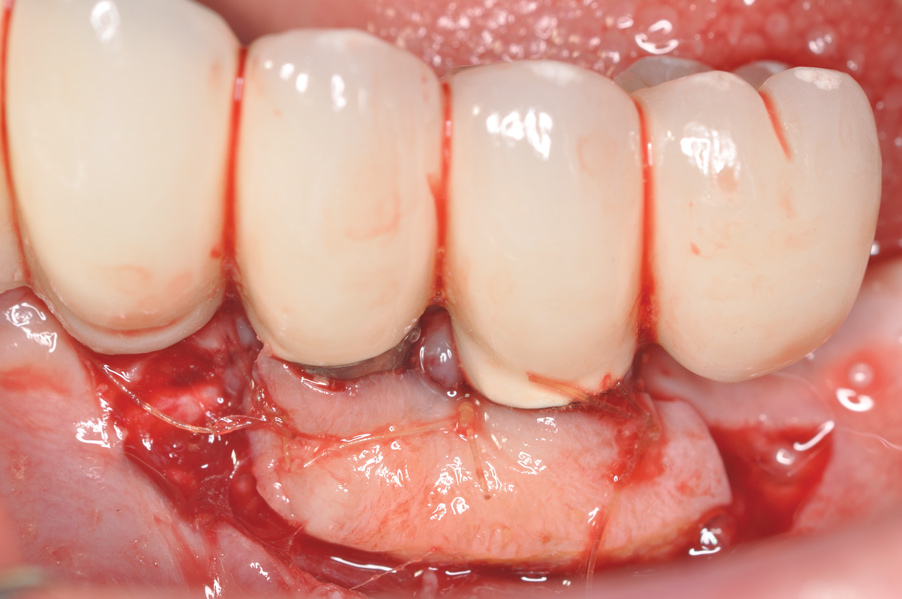

Fig 4. Clinical view of the area 3 months post-therapy. Shallow probings of 3 mm were present around the dental implants with absence of bleeding. However, the mucogingival deformities remained on the premolar implants and would require treatment.

Figure 4

Dental implants have revolutionized the way in which clinicians treat and restore partially and fully edentulous patients and have demonstrated success for managing a broad range of clinical dilemmas. While implants have been highly predictable and have achieved long-term success, they are not immune from complications associated with improper treatment planning, poor surgical and prosthetic execution, material failure, and inadequate or infrequent maintenance. Among these problems are the biologic complications of peri-implant mucositis and peri-implantitis, which are inflammatory conditions in the soft and/or hard tissues surrounding dental implants (Figure 1 through Figure 4).1,2